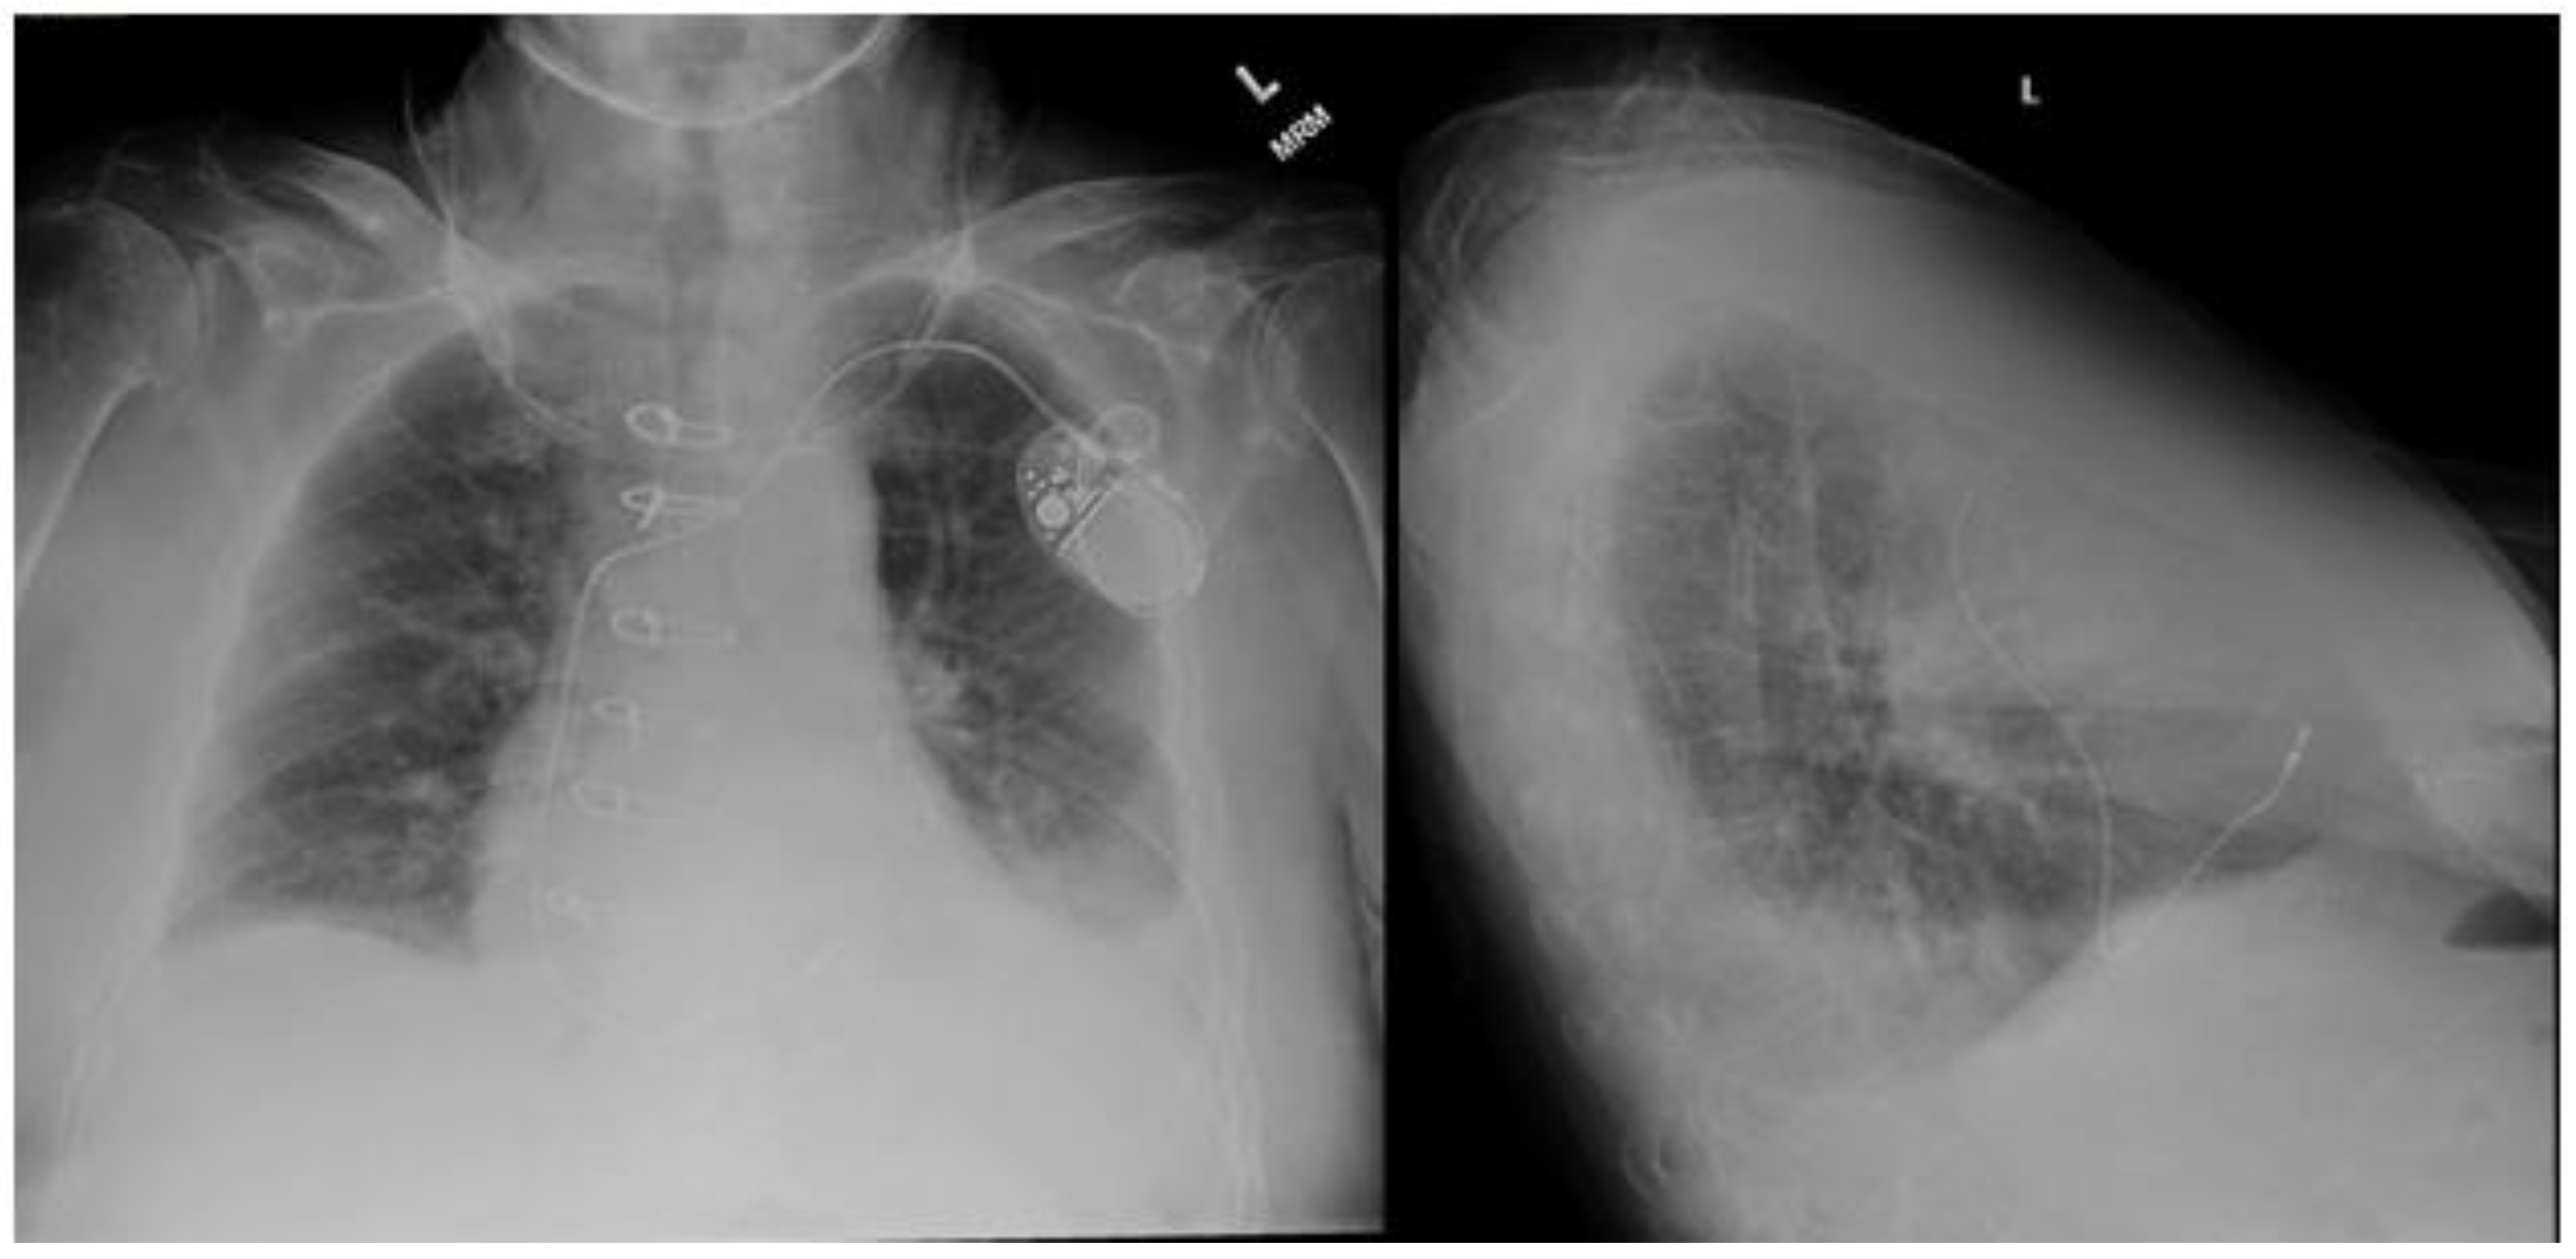

Standard posteroanterior and lateral chest radiography is often the initial modality employed to detect pleural effusion. On posteroanterior films, effusions are appreciated when the volume approaches 200 mL. Conversely, lateral views can visualize volumes as low as 50 mL [6]. In the intensive care setting, anteroposterior X-ray imaging is common, usually with the patient in a supine position. This positioning can cause pleural fluid to accumulate in the posterior thorax, making it less conspicuous on anteroposterior chest radiographs. In an upright patient, a pleural effusion typically presents on a chest X-ray as a uniform opacity in the lower lung field with blunting of the affected costophrenic angle (Figure 1). This effusion may display an upper border which curves up laterally, a radiological illusion created by a partially aerated lung between the anterior and posterior fluid layers known as the Ellis curve or meniscus sign [6]. Notably, a mediastinal shift away from the effusion is crucial for distinguishing pleural effusions from atelectasis. Utilizing lateral decubitus positioning to assess the layering of fluid is the most sensitive approach for detecting pleural effusions on chest radiographs. This positioning is capable of detecting effusions as small as 50 mL [7]. While chest radiography proves valuable in identifying pleural effusions, computed tomography and thoracic ultrasound offer greater sensitivity and detailed characterization of pleural fluid.

Figure 1.

Posteroanterior (PA) and lateral chest radiography demonstrating a left sided pleural effusion. Image courtesy of Abdelkader Mallouk, Radiopaedia.org, rID: 71570.